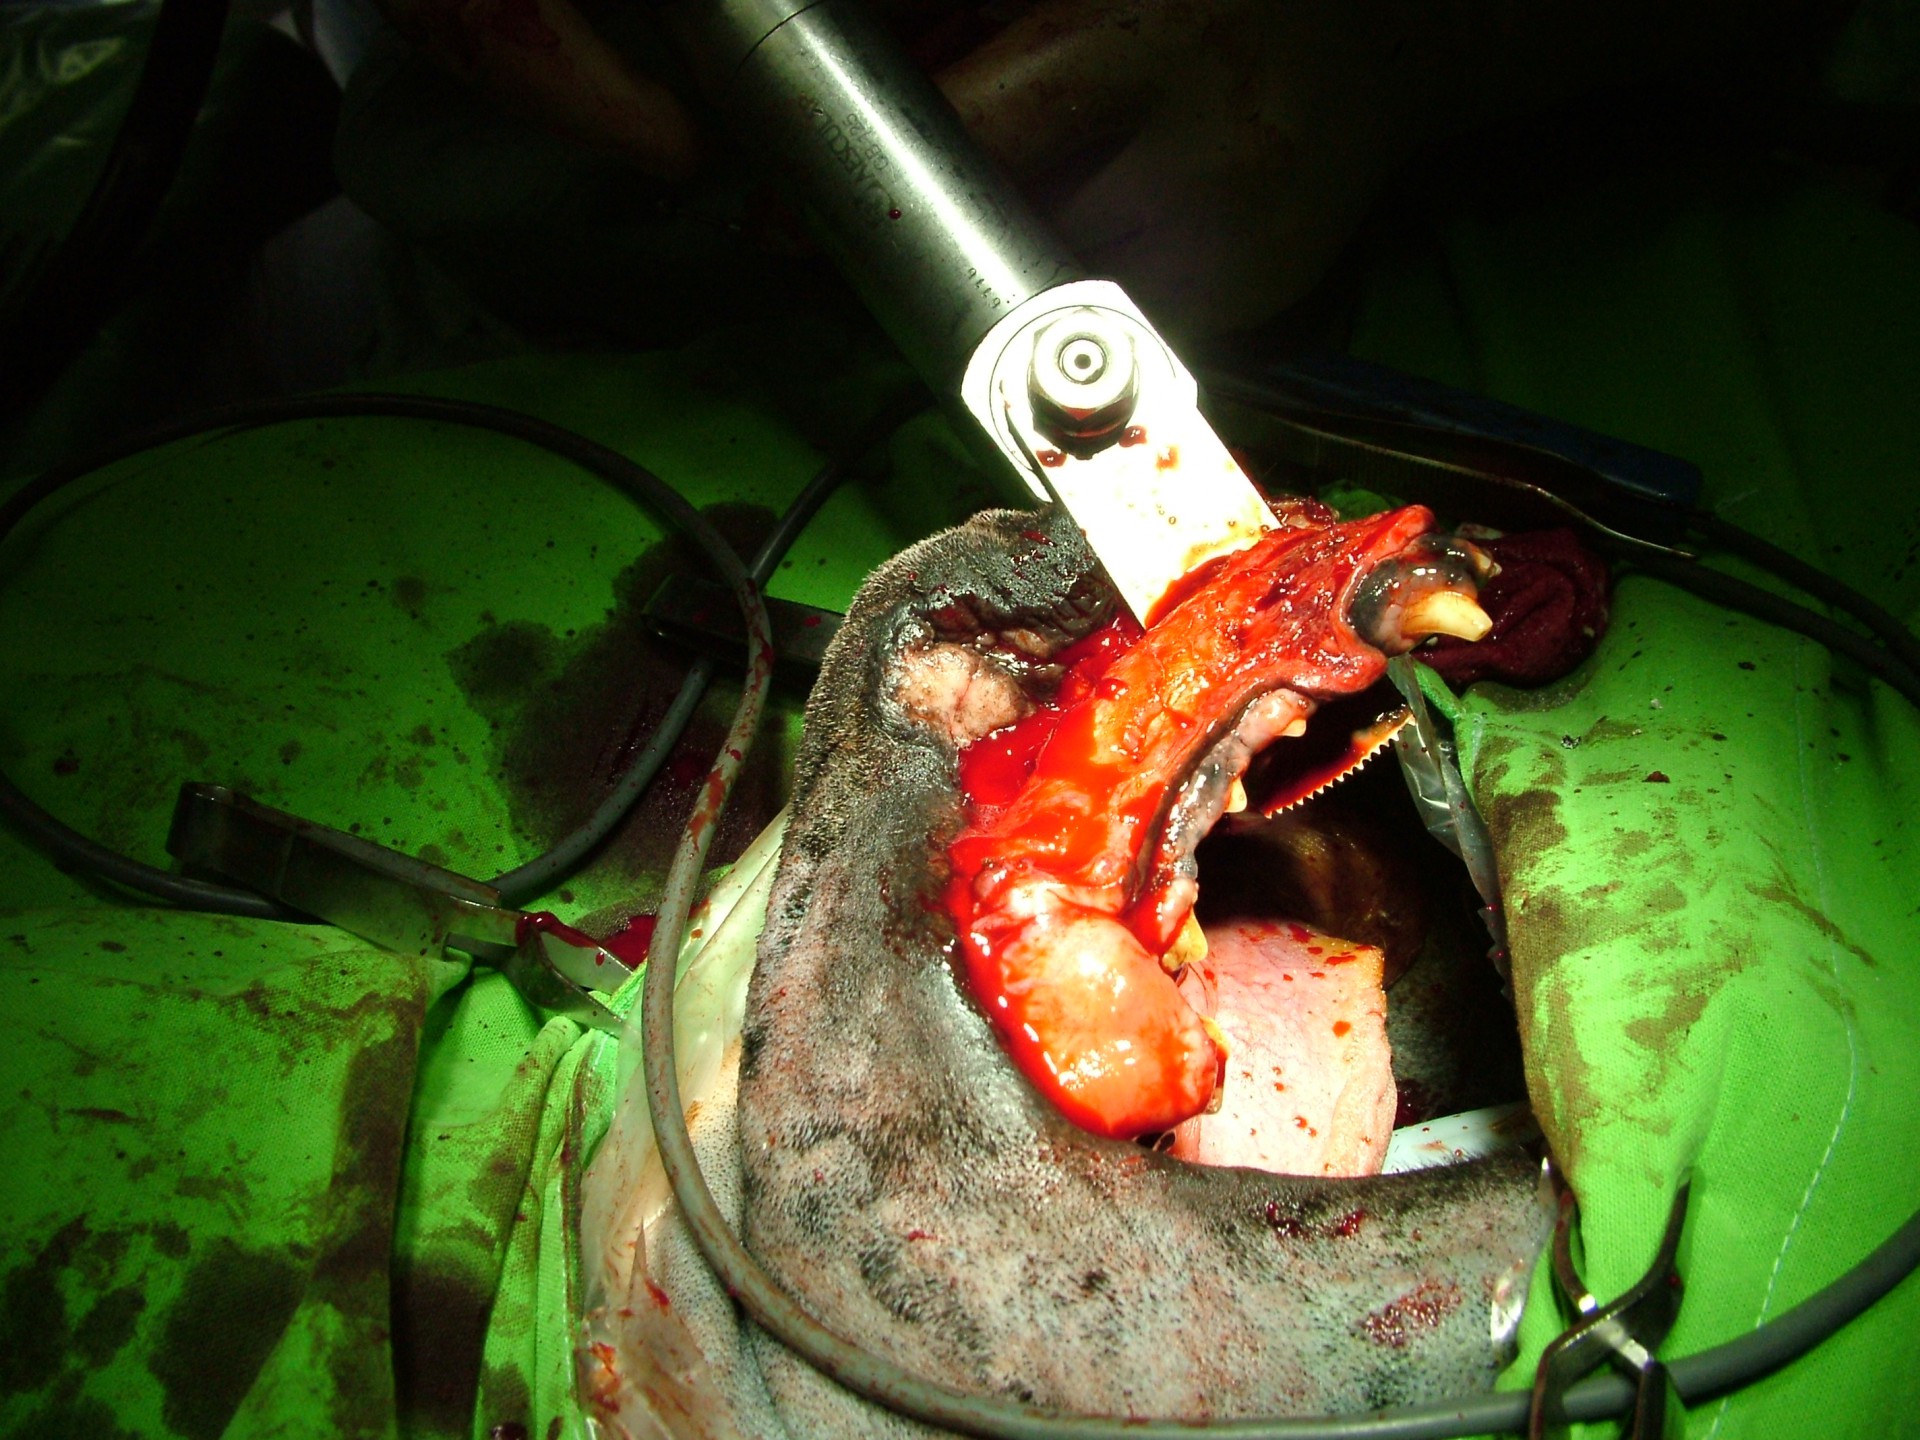

Az állkapocs környéki rosszindulatú daganatos elváltozások általában az állkapocs egyik szárát érintik, így a daganat eltávolításával együtt az érintett állkapocsrész is eltávolítandó (hemimandibulectomia). Az állkapocs egyik oldali szárának eltávolítását követően az azonos oldali pofák plasztikai jellegű igazítására is szükség van (cheiloplastica), mely a táplálékfelvételt segíti ill. a nyálcsorgást akadályozza meg.

Az állcsont környéki daganatok kimetszése során az állcsont érintett részét is eltávolítjuk, így az ezt követő legfontosabb feladat a száj- és az orrüreg integritásának megőrzése. Ezt a pofa nyálkahártyájából képzett lebeny segítségével oldjuk meg.